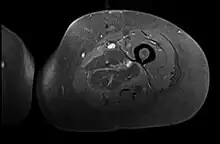

Creatine kinase may be normal or increased probably depending upon the stage of the condition when sampling is undertaken. ESR is elevated. Planar X-ray reveals soft tissue swelling and may potentially show gas within necrotic muscle, Bone scan may show non specific uptake later in the course. CT shows muscle oedema with preserved tissue planes (non-contrast enhancing). MRI is the exam of choice and shows increased signal on T2 weighted images within areas of muscle oedema. Contrast enhancement is helpful but must be weighed against the risk of Nephrogenic Systemic Fibrosis as many diabetics have underlying chronic kidney disease. Arteriography reveals large and medium vessel arteriosclerosis occasionally with dye within the area of tissue infarction. Electromyography shows non specific focal changes.